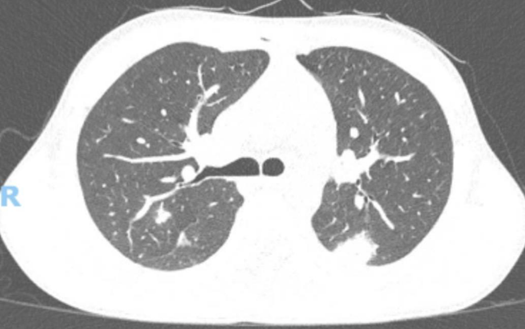

The Crack Lung – A Case Report

Débora Lopes, Cátia Gorgulho, Joana Ribeiro, André Neto Real, Nuno Catorze